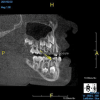

(8.) An original finding of a small lesion on the mesial root of tooth No. 30 was not accompanied by any outward symptoms; therefore, the patient delayed pursuing treatment. When a follow-up CBCT scan was acquired 6 years later, the easy-to-visualize increase in the dimensions of the lesion motivated the patient to elect a treatment plan.

Figure 8

(9.) An original finding of a small lesion on the mesial root of tooth No. 30 was not accompanied by any outward symptoms; therefore, the patient delayed pursuing treatment. When a follow-up CBCT scan was acquired 6 years later, the easy-to-visualize increase in the dimensions of the lesion motivated the patient to elect a treatment plan.

Figure 9

Identifying the shape and location of the roots of teeth to be removed is critical to performing safe exodontia. Some clinicians virtually deconstruct teeth using CBCT images prior to actually sectioning and removing them. Being able to recognize pathoses and differentiate affected structures from normal structures is key in deciding what the treatment should be and when that treatment should be initiated (Figure 8 through Figure 10). The arena of the oral surgeon is larger than that of many general practitioners, involving the sinuses and condyles and other considerations in and around the entire mandible and maxilla. Certain fractures and other conditions that some general practitioners feel uncomfortable treating are often referred for evaluation and treatment by an oral surgeon. Because of this, oral surgeons require the most accurate and complete diagnostic information available. The American Academy of Oral and Maxillofacial Radiology recommends that "cross-sectional imaging be used for the assessment of all dental implant sites" and has stated that "CBCT is the imaging method of choice for gaining this information."18